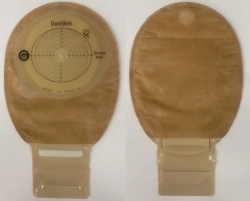

Medical product is intended for use in colostomies, ileostomies and urostomies for hermetic and secure attachment of stoma bags to the skin of the anterior abdominal wall, as well as to protect the skin of the peristomal area from stoma secretions and preserve the physiological functions of the skin due to the absorption of natural skin moisture (sweat, sebum).